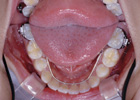

2.ブラケット:

歯に装置を接着して、ワイヤーを用いて歯並びを治します。

<裏側矯正装置>